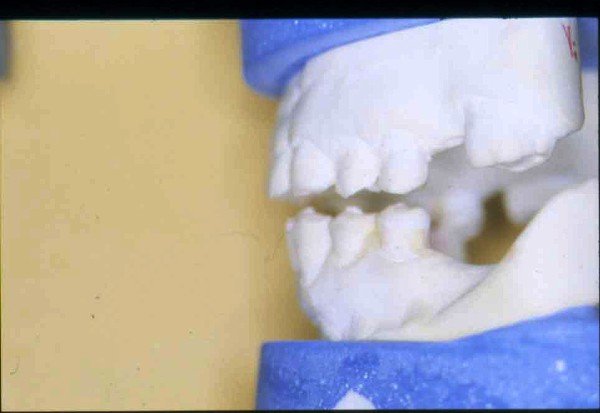

APRECIACIONES DIAGNÓSTICAS EN BASE A LA APERTURA MENTAL DEL CLÍNICO FRENTE A LO QUE EL PACIENTE PROPONE EN MUCHAS OCASIONES , LA DEMANDA DE LOS PACIENTES NOS INCLINAN A FOCALIZAR NUESTRA ATENCIÓN EN LAS PIEZAS DE LAS CUALES EL ENFERMO SE QUEJA. PACIENTE SEXO FEMENINO, 55 AÑOS, SE PRESENTA A LA CONSULTA DERIVADA POR COMPAÑERO GENERALISTA, QUIEN LLEVA MESES PROCEDIENDO A LA «DESINFECCIÓN» DE UN PRIMER PREMOLAR IZQUIERDO, EL QUE SE PRESENTA ABIERTO EN SU CONDUCTO EN EL AFÁN DE PERMITIR EL ESCAPE DE GASES DE UNA GANGRENA PULPAR. A LA INSPECCIÓN CLÍNICA SE OBSERVAN FACETAS PARAFUNCIONALES DE TERCER GRADO , ASINTOMÁTICAS, CON EVIDENTES DIFICULTADES MASTICATORIAS Y ESTÉTICAS , FALTA TOTAL DE SUS MOLARES INFERIORES, Y ADELANTAMIENTO PRONUNCIADO DE SU MANDIBULA, LA QUE CUESTA MANIPULAR DEBIDO A LA SITUACIÓN DE ESPASMO DE CASI TODA SU MUSCULATURA GNATICA. SE ESTUDIA EL CASO RADIOLOGICAMENTE, Y SE RELAJA EL SISTEMA MEDIANTE LAM. DE LONG REALIZANDO UN MONTAJE EN LA ORC OBTENIDA. NO SATISFECHOS CON EL RESULTADO, CONFECCIONAMOS UN JIG DE LUCIA, EL QUE DEJAMOS EN BOCA TODA UNA NOCHE, AL CABO DE LA CUAL REALIZAMOS UN NUEVO REGISTRO REALIZAMOS UN ENCERADO RÁPIDO DEL CASO, Y CONFECCIONAMOS UNA ESTRUCTURA OCLUSAL PLASTICA, QUE ADEMÁS REPONGA EL ASPECTO ESTÉTICO PERDIDO (FÉRULA DE RELAJACIÓN DE COMPONENTE ESTÉTICO), LO QUE PERMITE AL ENFERMO LUEGO DE DOS DÍAS DE USO, NO SOLO CORROBORAR LA COMODIDAD MASTICATORIA Y LA FALTA DE SÍNTOMAS MUSCULARES, SINO TAMBIÉN OBSERVAR APROXIMADAMENTE LA DIFERENCIA ENTRE LA SITUACIÓN INICIAL Y LO QUE PUEDE LOGRARSE MEDIANTE EL TRATAMIENTO. EL PACIENTE ADVIERTE LA MEJORÍA DE LA SITUACIÓN. ACEPTADO POR PARTE DEL MISMO EL TRATAMIENTO SUGERIDO, CREAMOS UN JUEGO COMPLETO DE PROVISORIOS EN BASE AL ENCERADO, Y PROCEDEMOS A TRATAR LA INFRAESTRUCTURA, QUE CONSISTE EN LAS ENDODONCIAS, SUS REFUERZOS A PERNOS DE ORO, LOS ASPECTOS PERIODONTALES DEL CASO, Y DOS IMPLANTES INFERIORES CON TÉCNICA SEMISUMERGIDA ,DE 5 MM DE ANCHO POR 12 DE LONGITUD, CON ANILLO DE ZIRCONIO , A LA ESPERA DE OSTEOINTEGRACIÓN, TRANSCURREN TRES MESES EN EL USO DE UNA NUEVA OCLUSIÓN CONSTITUIDA POR LOS PROVISIONALES, SEGÚN EL ENCERADO, QUE SE REALIZÓ SIGUIENDO LOS CÁNONES DE UNA OCLUSIÓN ORGÁNICA. COMPROBADA LA EFICACIA DE LA NUEVA SITUACIÓN, CON SUS DISCLUSIONES LATERALES Y POSTERO ANTERIORES CORRECTAS, CARECIENDO YA DE SINTOMATOLOGÍA MUSCULAR (SIN MIALGIAS, SIN MIOSITIS, Y CON UN GRADO DE APERTURA DE 4,50 CM), Y SIN SIGNOS EVIDENTES DE DESGASTE SOBRE EL MATERIAL DE LOS PROVISORIOS, ES DECIR: VERIFICANDO QUE EL PACIENTE YA NO BRUXA, VERTICALIZANDO EL CICLO MASTICATORIO /OTORGANDO ORC/ DIMENSIÓN VERTICAL /PROTEGIENDO A LAS PIEZAS `POSTERIORES DE IMPACTOS LATERALES RECIEN ENTONCES , MONTAMOS EN ARTICULADOR SEMI AJUSTABLE LOS MODELOS DE TRABAJO DEFINITIVOS. CONFECCIONAMOS ENTONCES LAS COFIAS INFRA PORCELANA, EN PORCELANA DE ALTA DENSIDAD EN EL SECTOR ANTERIOR Y EN ORO GALVÁNICO PARA EL SECTOR POSTERIOR PARA LUEGO COMPLETAR LA GUIA ANTERIOR , VERIFICANDO LA ALTURA DE LOS INFERIORES RESPECTO DEL LABIO INFERIOR Y CORROBORANDO LOS PUNTOS DE CONTACTOS INTER CANINOS, QUE CENTRALIZAN LA MANDIBULA Y VERTICALIZAN EL CICLO MASTICATORIO Y LAS DISCLUSIONES CANINAS QUE OTORGARÁN PROTECCIÓN A LOS SECTORES POSTERIORES. POSTERIORMENTE CHEQUEAMOS LA DISCLUSIÓN EN PROPULSIVA DE LA GUIA ANTERIOR YA TERMINADA. FIG38 FIG39 UNA VEZ OBTENIDO UN COMANDO ANTERIOR EFECTIVO, COMO LO ES LA GUIA ANTERIOR CON TODOS SUS COMPONENTES, PROCEDEMOS A REALIZAR LAS TABLAS PREMOLAR / MOLAR DE AMBOS LADOS Y OBSERVAMOS QUE LOS PUNTOS INTEROCLUSALES DE CONTACTO SEAN SUFICIENTES Y CUMPLAN SU OBJETIVO DE OTORGAR ESTABILIDAD MESIO DISTAL Y VESTÍBULO LINGUAL. TRANSCURRIDO UN AÑO DE FINALIZADO EL TRATAMIENTO, REALIZAMOS UN CHEQUEO POST OPERATORIO DEL CASO, EN TODOS LOS PARÁMETROS ANTERIORMENTE MENCIONADOS, Y OBSERVAMOS LA ABSOLUTA ESTABILIDAD DEL MISMO EN TODOS SUS NIVELES Y TEJIDOS.